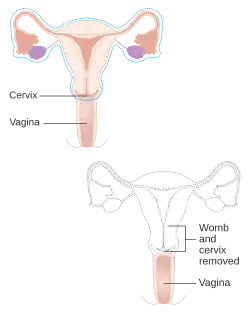

Diagram showing what is removed with a radical hysterectomy | |

Hysterectomy is the surgical removal of the uterus and cervix. Supracervical hysterectomy refers to the removal of the uterus while the cervix is spared. These procedures may also involve removal of the ovaries (oophorectomy), fallopian tubes (salpingectomy), and other surrounding structures. The terms “partial” or “total” hysterectomy are lay terms that incorrectly describe the addition or omission of oophorectomy at the time of hysterectomy. These procedures are usually performed by a gynecologist. Removal of the uterus is a form of sterilization, rendering the patient unable to bear children (as does removal of ovaries and fallopian tubes) and has surgical risks as well as long-term effects, so the surgery is normally recommended only when other treatment options are not available or have failed. It is the second most commonly performed gynecological surgical procedure, after cesarean section, in the United States.[1] Nearly 68 percent were performed for conditions such as endometriosis, irregular bleeding, and uterine fibroids.[1] It is expected that the frequency of hysterectomies for non-malignant indications will continue to fall, given the development of alternative treatment options.[2]

Types

Hysterectomy, in the literal sense of the word, means merely the removal of the uterus. However, other organs such as the ovaries, fallopian tubes, and the cervix are very frequently removed as part of the surgery.[60]

- Radical hysterectomy: complete removal of the uterus, cervix, upper vagina, and parametrium. Indicated for cancer. Lymph nodes, ovaries, and fallopian tubes are also usually removed in this situation, such as in Wertheim's hysterectomy.[61]

- Total hysterectomy: complete removal of the uterus and cervix, with or without oophorectomy.

- Subtotal hysterectomy: removal of the uterus, leaving the cervix in situ.